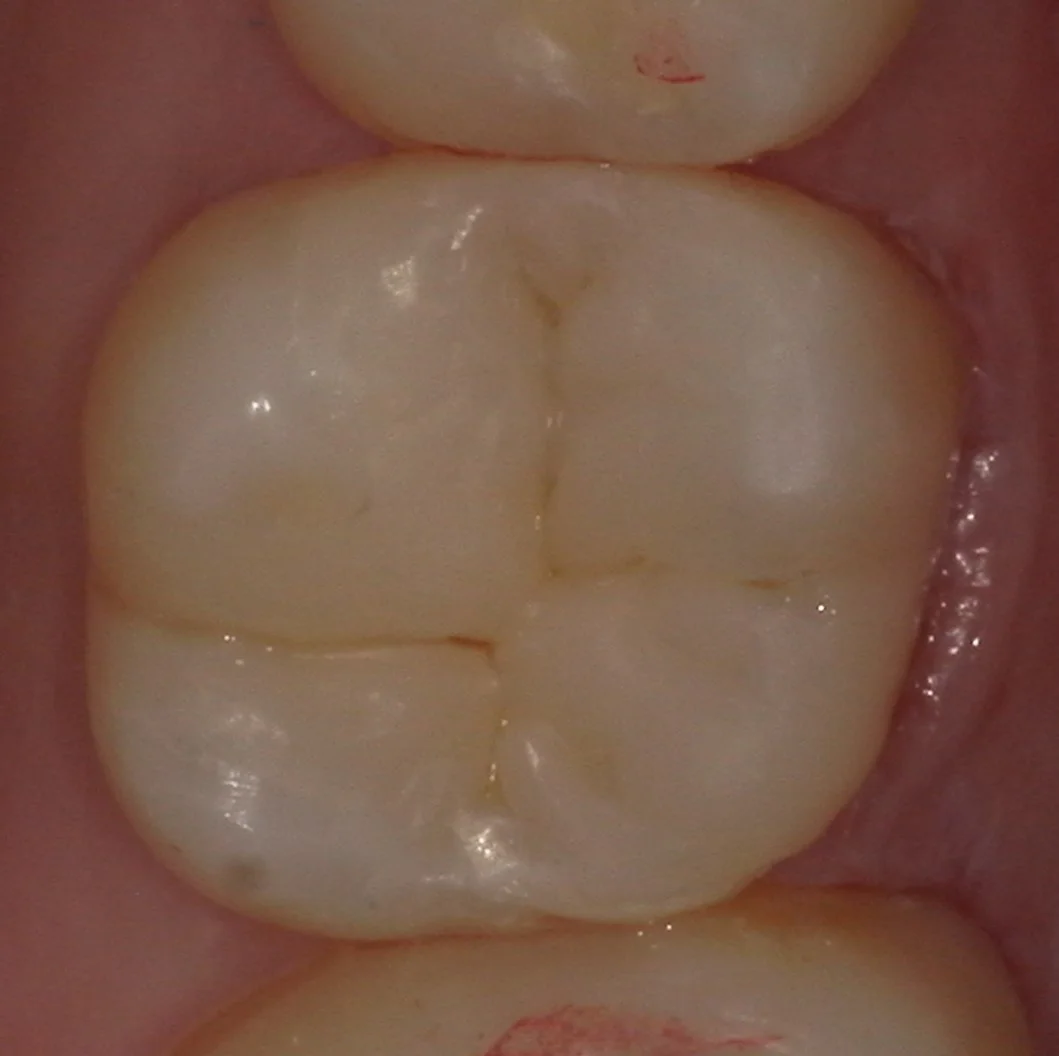

そして、最後、詰め終わって噛み合わせの調整・研磨まで終了したのがこちらになります。

まず、噛む面です。

続いて、側面。

歯の形態が違和感なく自然に仕上げられたかと思います。

随分とご自身の歯を失っていましたが、無事に残っている歯も亀裂が入ることなく詰め終わることが出来ました。

この処置後、また別の処置で来院された際に症状について聞いてみましたが、何の問題もなく生活出来ているようで良かったです。